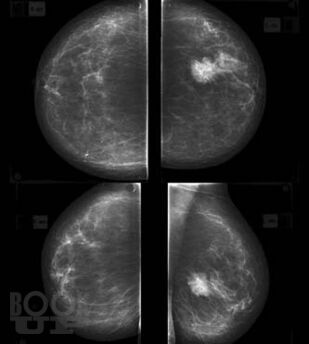

В основу книги положены материалы собственных исследований авторов и практический опыт использования комплекса новейших методик ультразвукового исследования в диагностике рака молочной железы, изучении состояния регионарных зон лимфоотока. Цель книги – помочь практикующим специалистам ультразвуковой, лучевой диагностики, маммологам, гинекологам, врачам общей практики систематизировать знания по эффективному использованию в своей практике новейших технологий ультразвукового исследования, обучить основам комплексной первичной и дифференциальной диагностики патологии молочных желез. Издание хорошо иллюстрировано, содержит большое количество рисунков, эхограмм.